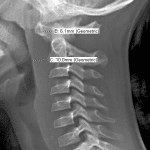

Age: 7

Sex: Male

Indication: Trauma

Case #12

Findings

- Slight widening of the atlantodental interval

- Prevertebral edema in the upper and mid cervical spine

Diagnosis

- Prevertebral edema

Slight widening of the atlantodental interval with upper and mid cervical prevertebral edema, concerning for ligamentous injury. Recommend MRI for further evaluation.

No evidence of acute displaced fracture.